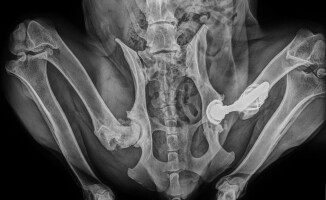

Bezdomna Klara potrzebuje nowego biodra. Suczka owczarka jest podopieczną stowarzyszenia Pieski Instytut Pomocy z Piły.

Klara to stosunkowo młody pies, bo ma około 5 lat, ale jej stan bioder jest katastrofalny. Weterynarze jednoznacznie orzekli konieczność endoprotezowania, aby pies mógł chodzić. W kwietniu udało się przeprowadzić pierwszy zabieg, kolejny jest zaplanowany w październiku, jednak wciąż brakuje pieniędzy. Endoproteza kosztuje 15 tys. zł. Na koncie zrzutki jest już ponad 5 tys. zł. Ale to wciąż za mało.

- Pierwszy zabieg był obarczony dużym ryzykiem, ponieważ biodra Klary praktycznie nie istniały, zwyrodnienia były tak wielkie, że staw trzeba było „stworzyć” od nowa. Już po dwóch miesiącach od operacji było widać, że Klara chętniej korzysta z nowego biodra, niż ze starego, które wciąż niemiłosiernie boli. Dlatego ponownie zwracam się do wszystkich ludzi dobrej woli o pomoc. Bez Was nie dam rady. Grosz do grosza i musi się udać, chociaż czasy są bardzo ciężkie. Zachęcam do wpłat cyklicznych - na przykład co miesiąc drobna sumka dla Klary. Liczy się każda, nawet najmniejsza wpłata, dlatego proszę - udostępniajcie zrzutkę gdzie się da, opowiadajcie o Klarze znajomym i przyjaciołom - prosi Beata Januszewska z Pieskiego Instytutu Pomocy w Pile.